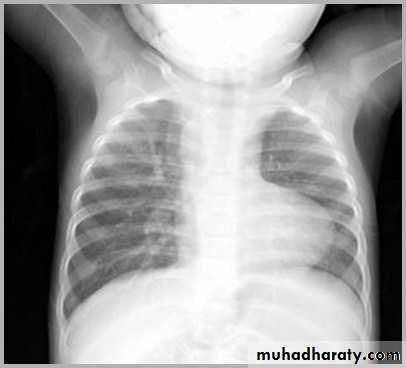

"boot shaped" heart ( TOF )

TOF

Radiographic features

Plain film

Plain films may classically show :

1. "boot shaped" heart with an upturned cardiac apex due to right ventricular hypertrophy and concave pulmonary arterial segment.

2.Pulmonary oligaemia due to decreased pulmonary arterial flow.

3.Right sided aortic arch is seen in 25%.